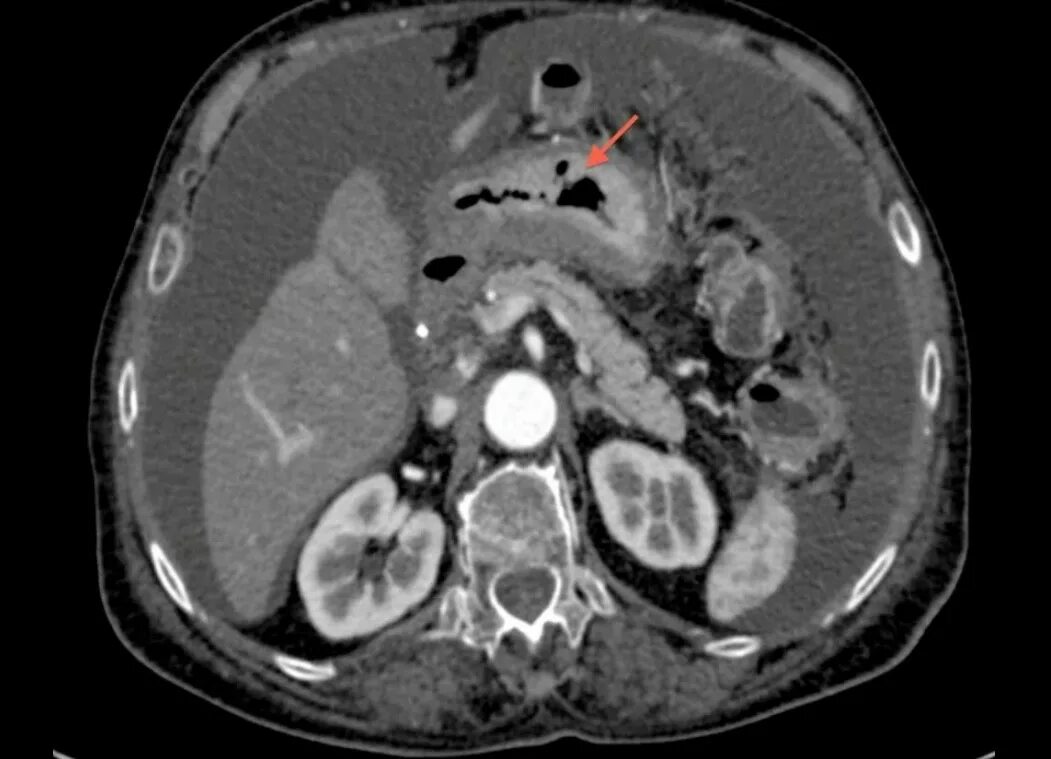

Язва желудка кт